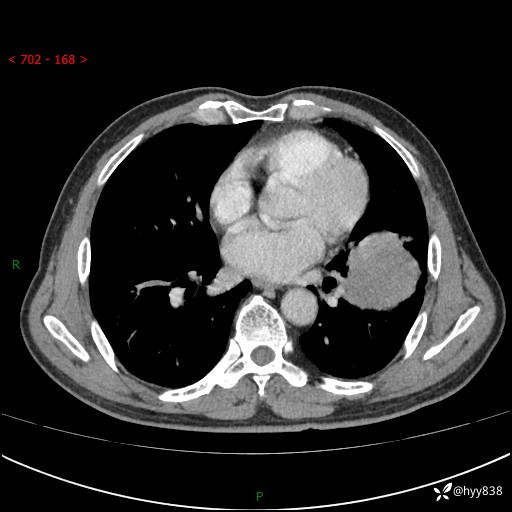

68岁/男,发现左下肺占位5天。如此大的肿块,患者竟然没有症状---结果公布~

【患者信息】:68岁/男

【主诉】:检查发现左下肺占位5天。

【现病史及既往史】:患者于4天前外院行“经尿道钬激光碎石术”,住院期间胸部CT检查发现左下肺肿块,患者平素无明显咳嗽咳痰,无心慌、胸闷、胸痛、呼吸困难、低热、盗汗,无头痛、头晕,无腹痛、腹胀等不适,现患者为求进一步治疗,遂来我院就诊,以“左下肺肿块”收入我科。 患者自起病以来,精神可,睡眠可,饮食可,大小便正常,体重无明显改变。

【检查】:胸部CT增强扫描